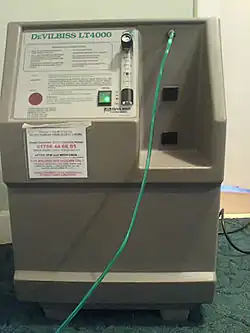

Uptake of O

2 from the air is the essential purpose of respiration, so oxygen supplementation is used in medicine. Treatment not only increases oxygen levels in the patient's blood, but has the secondary effect of decreasing resistance to blood flow in many types of diseased lungs, easing work load on the heart. Oxygen therapy is used to treat emphysema, pneumonia, some heart disorders (congestive heart failure), some disorders that cause increased pulmonary artery pressure, and any disease that impairs the body's ability to take up and use gaseous oxygen.[119]

Treatments are flexible enough to be used in hospitals, the patient's home, or increasingly by portable devices. Oxygen tents were once commonly used in oxygen supplementation, but have since been replaced mostly by the use of oxygen masks or nasal cannulas.[120]

Hyperbaric (high-pressure) medicine uses special oxygen chambers to increase the partial pressure of O

2 around the patient and, when needed, the medical staff.[121] Carbon monoxide poisoning, gas gangrene, and decompression sickness (the 'bends') are sometimes addressed with this therapy.[122] Increased O

2 concentration in the lungs helps to displace carbon monoxide from the heme group of hemoglobin.[123][124] Oxygen gas is poisonous to the anaerobic bacteria that cause gas gangrene, so increasing its partial pressure helps kill them.[125][126] Decompression sickness occurs in divers who decompress too quickly after a dive, resulting in bubbles of inert gas, mostly nitrogen and helium, forming in the blood. Increasing the pressure of O

2 as soon as possible helps to redissolve the bubbles back into the blood so that these excess gasses can be exhaled naturally through the lungs.[119][127][128] Normobaric oxygen administration at the highest available concentration is frequently used as first aid for any diving injury that may involve inert gas bubble formation in the tissues. There is epidemiological support for its use from a statistical study of cases recorded in a long term database.[129][130][131]